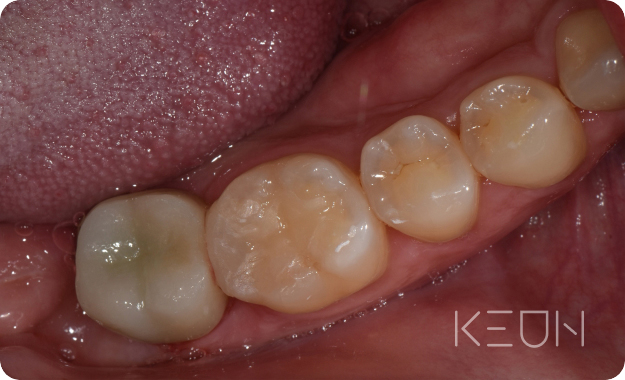

충치&신경 재치료.

충치 재치료

처음 충치 치료를 할 때 대부분 보철물을 씌우는 충전치료를 하는데요, 치아와의 틈이나 경계 없이 치료가 이루어집니다. 보철물의 수명은 관리에 따라 다르지만 보통 5~8년 정도로 시간이 지나면 재료도 오래되고, 치아의 틈 사이로 음식물이 낄 수 있습니다. 제대로 제거가 되지 않으면 2차 충치가 생기기도 합니다. 또한 입안에는 항상 세균이 상주하고 있어 관리가 소홀해지면 충치가 발생하기 쉽습니다.

- Before

- After